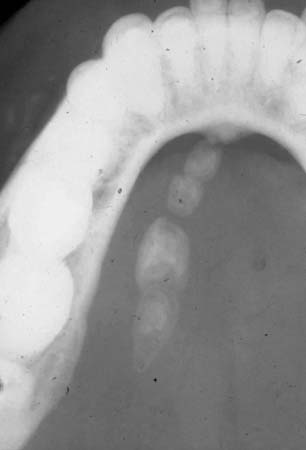

In the presence of a submandibular swelling suspicious of a neoplasm, ultrasound or CT scan and fine needle aspiration cytology are recommended. This may be sufficient to diagnose chronic sclerosing sialadenitis and thus reserve surgical removal of the gland for symptomatic cases. Scintigraphy with radiolabelled Tc-99 may be helpful in diagnosing a hypofunctional salivary gland accompanying chronic sclerosing sialadenitis, prior to consideration of surgery.[26] If subacute necrotising sialadenitis is suspected, a biopsy can confirm the diagnosis and differentiate it from necrotising sialometaplasia.[Figure caption and citation for the preceding image starts]: Occlusal radiographic film showing presence of multiple sialoliths in the left Wharton's ductFrom the personal collection of Dr A. Aguirre; used with permission [Citation ends].